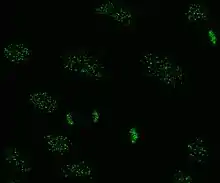

Indirect immunofluorescence

Indirect immunofluorescence is one of the most commonly used tests for ANAs. Typically, HEp-2 cells are used as a substrate to detect the antibodies in human serum. Microscope slides are coated with HEp-2 cells and the serum is incubated with the cells. If the said and targeted antibodies are present then they will bind to the antigens on the cells; in the case of ANAs, the antibodies will bind to the nucleus. These can be visualised by adding a fluorescent tagged (usually FITC or rhodopsin B) anti-human antibody that binds to the antibodies. The molecule will fluoresce when a specific wavelength of light shines on it, which can be seen under the microscope. Depending on the antibody present in the human serum and the localisation of the antigen in the cell, distinct patterns of fluorescence will be seen on the HEp-2 cells.[51][52] Levels of antibodies are analysed by performing dilutions on blood serum. An ANA test is considered positive if fluorescence is seen at a titre of 1:40/1:80. Higher titres are more clinically significant as low positives (≤1:160) are found in up to 20% of healthy individuals, especially the elderly. Only around 5% of the healthy population have ANA titres of 1:160 or higher.[8][53]

There are many nuclear staining patterns seen on HEp-2 cells: homogeneous, speckled, nucleolar, nuclear membranous, centromeric, nuclear dot and pleomorphic. The homogeneous pattern is seen when the condensed chromosomes and interphase chromatin stain. This pattern is associated with anti-dsDNA antibodies, antibodies to nucleosomal components, and anti-histone antibodies. There are two speckled patterns: fine and coarse. The fine speckled pattern has fine nuclear staining with unstained metaphase chromatin, which is associated with anti-Ro and anti-La antibodies. The coarse staining pattern has coarse granular nuclear staining, caused by anti-U1-RNP and anti-Sm antibodies. The nucleolar staining pattern is associated with many antibodies including anti-Scl-70, anti-PM-Scl, anti-fibrillarin and anti-Th/To. Nuclear membrane staining appears as a fluorescent ring around the cell nucleus and are produced by anti-gp210 and anti-p62 antibodies. The centromere pattern shows multiple nuclear dots in interphase and mitotic cells, corresponding to the number of chromosomes in the cell. Nuclear dot patterns show between 13 and 25 nuclear dots in interphase cells and are produced by anti-sp100 antibodies. Pleomorphic pattern is caused by antibodies to the proliferating cell nuclear antigen.[26][53][57][58] Indirect immunofluorescence has been shown to be slightly superior compared to ELISA in detection of ANA from HEp-2 cells.[54]